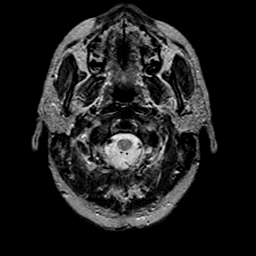

glioma overlay -- Slice #1

[Home][Help][Clinical] Slice 1